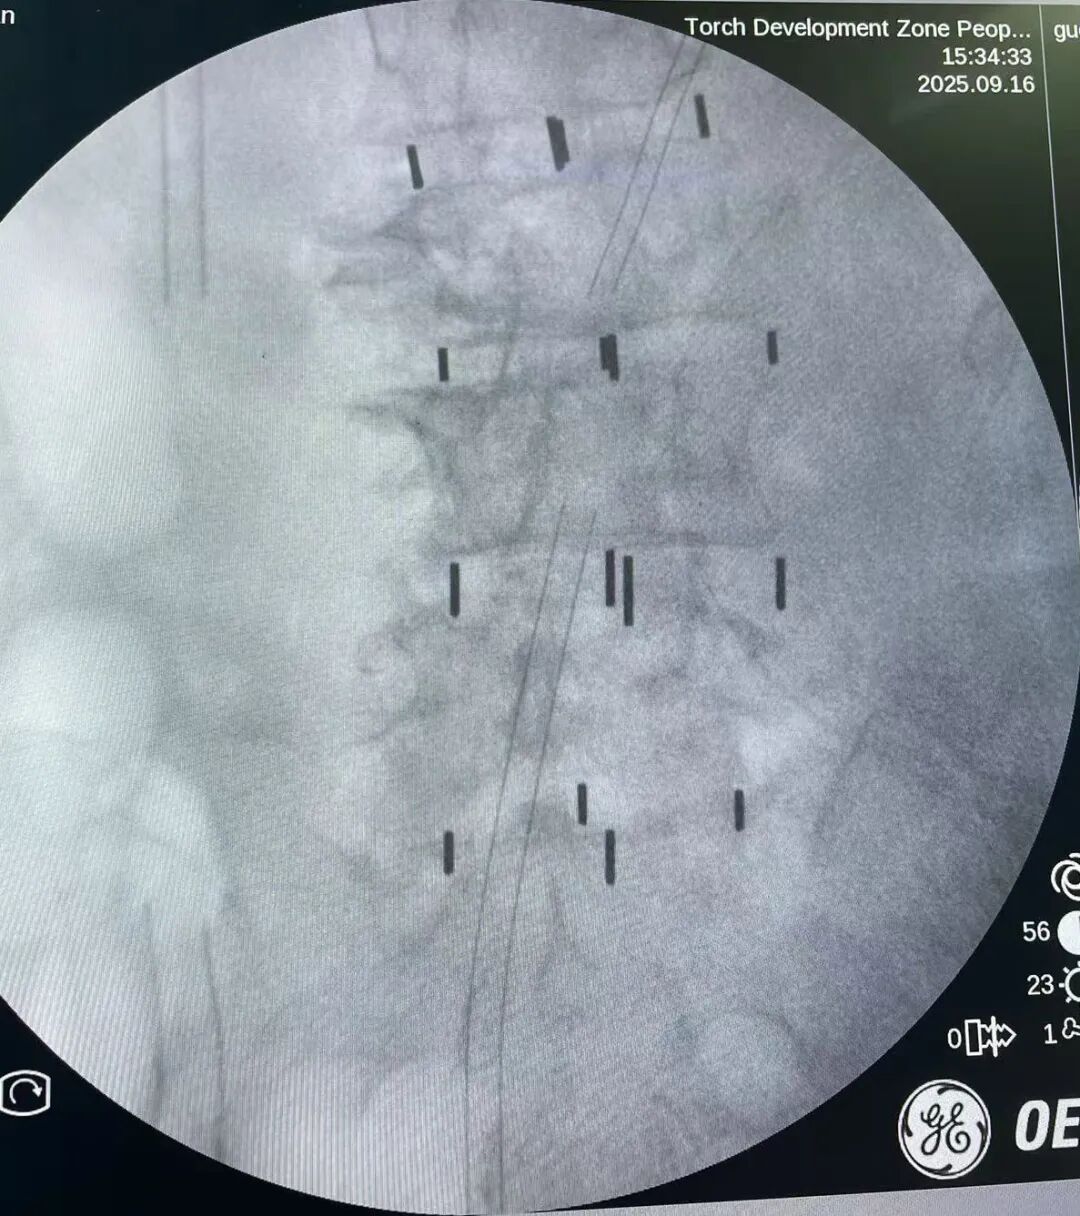

第一階段,運(yùn)用XLIF技術(shù),在患者腰部左側(cè)方間隔做兩個(gè)長約4厘米的小切口,從身體側(cè)面腹膜后間隙通過擴(kuò)張管道精準(zhǔn)直達(dá)腰椎椎間隙。醫(yī)生切除嚴(yán)重退變的椎間盤組織,并于椎間植入融合器。